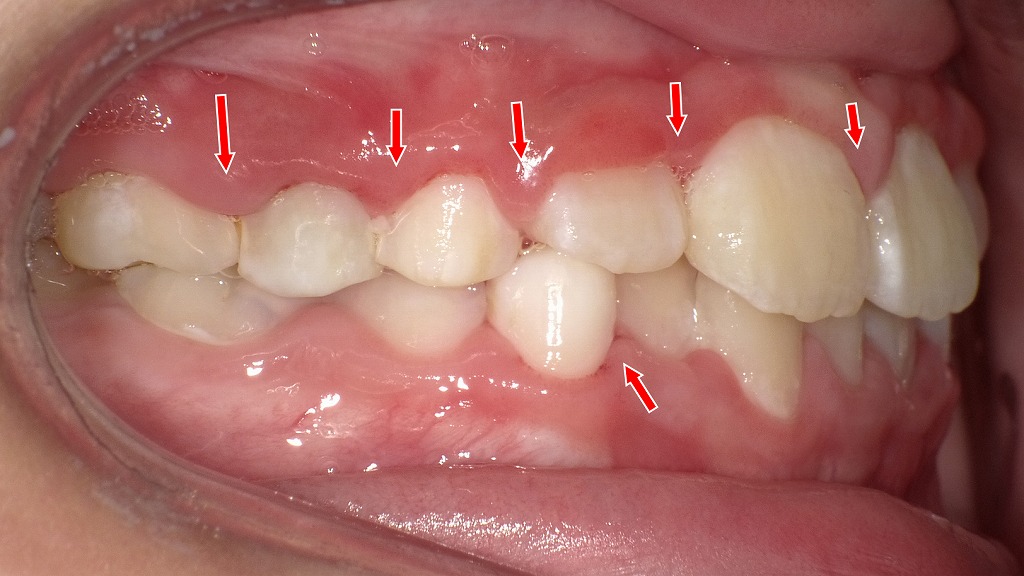

🖼 画像③(右側面):

■ 右側も同様に歯ぐき全体が発赤

矢印部分に沿って、

歯ぐきのふくらみ・赤み・プラークの付着が確認できます。

■ 下の前歯はプラークがつきやすい部位

下顎前歯の裏側は唾液の影響で歯石が付きやすく、

子どもでもプラークや歯肉炎が起きやすい典型的な場所です。

✔ 子どもの歯肉炎の典型例

生え変わり時期は、歯列がデコボコになるため磨きづらく、

プラークが溜まり→歯ぐきが赤く腫れ→触れると出血する

という流れが起こりやすくなります。

✔ 痛みがなくても進行する

軽度の歯肉炎は痛みを感じにくいため、

周囲が気づかないうちに炎症が広がることがあります。

✔ 毎日の仕上げ磨き・染め出しが効果的

改善のポイントは

「プラークを落とし切ること」

です。

特に、

- 歯と歯ぐきの境目

- 生えかけの永久歯の周り

- 奥歯の溝・段差

を意識して磨くと炎症は改善しやすくなります。